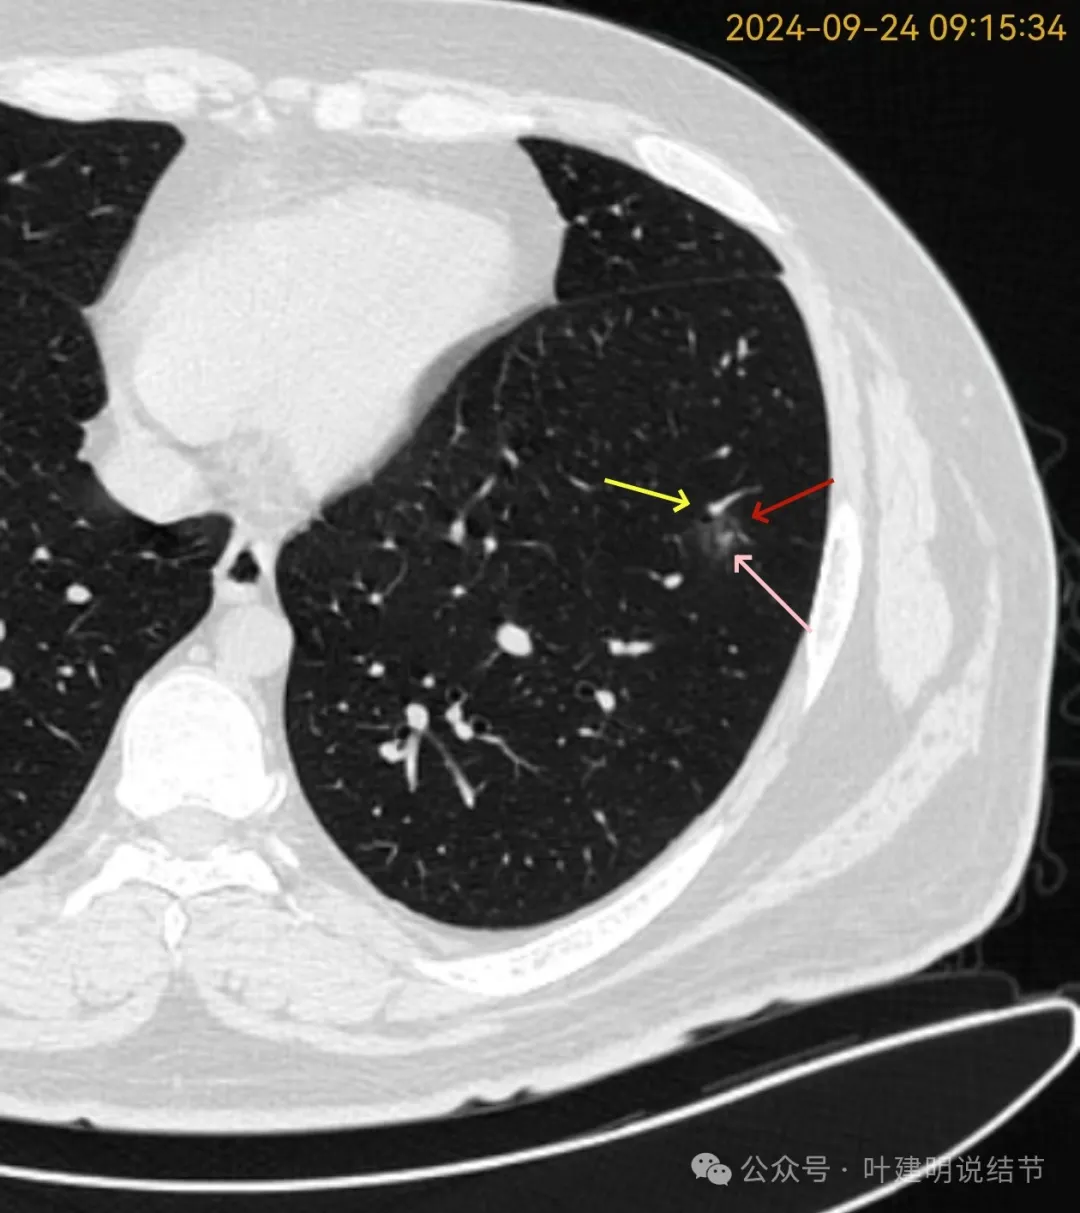

再看2024年9月复查的片子:

病灶出现,磨玻璃密度。有微小血管与细支气管通气征。

邻近细支气管扩张、边缘细毛刺、整体轮廓清。

有毛刺征,整体轮廓清,与血管之间间隙消失。

毛刺、血管征、邻近支气管扩张、整体轮廓清,病灶与血管间隙消失。

有少许偏实性成分,整体轮廓清。

纯磨密度,不太纯,血管贴边,血管与病灶间隙消失,整体轮廓与瘤肺边界清。

血管弯征可见、细毛刺明显、细支气管扩张,血管进入。

密度总体不高,轮廓与边界清楚。

密度较淡,轮廓较清。

边缘区密度淡且较纯,轮廓清楚。